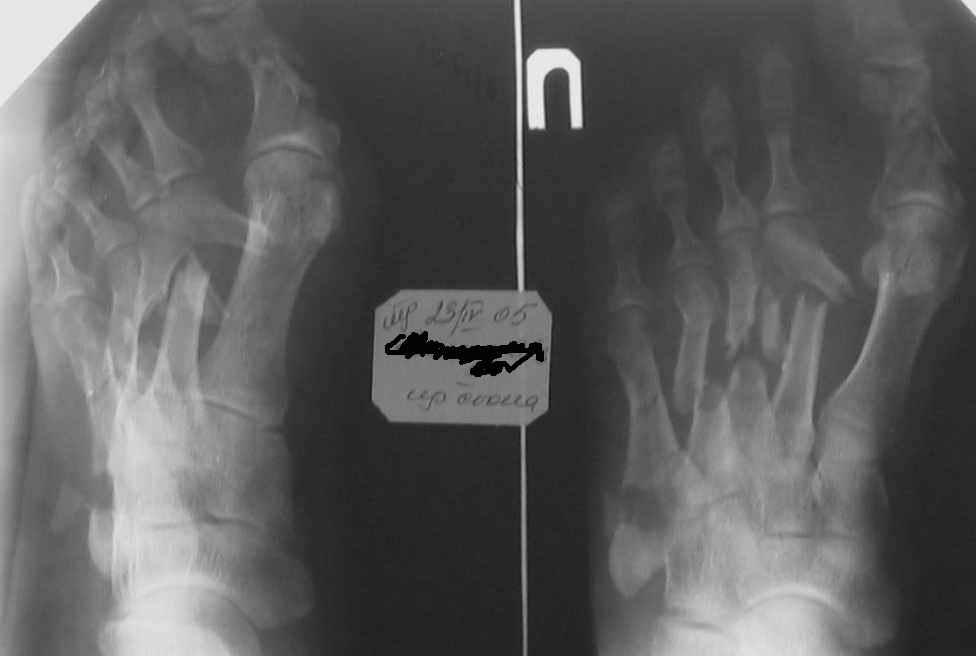

Уважаемые коллеги! Мужчина 51 год, 23 апреля 2005 года на стопу упала мет. балка. Получил открытые переломы плюсневых костей.

При поступлении ПХО, гипсовая лонгета, на следующий день множественные фликтены. Стабилизация в АВФ на третий день. В дальнейшем, по всей видимости, компартмент синдром с некрозом участка кожи на тыле стопы. Проводились этапные некрэктомии, в т. ч. дезартикуляция второго пальца. К сожалению, в силу сложившихся обстоятельств, пациент побывал в руках не единственного хирурга (не отрицаю в первую очередь своих). Дальнейшее лечение - консервативное, направленное на заживление раны. Аппарат демонтирован через 3 месяца. Сейчас ходит с небольшой нагрузкой. Прошу указать на допущенные по Вашему мнению тактические ошибки и дать советы по дальнейшему ведению больного. С уважением, А.Минервин. О себе: Минервин Алексей, заведующий травматологическим отделением ГБ 3 г. Муром, Владимирской области.

Дальнейшее ведение Вашего пациента, по моему мнению, должно свестись к коррекции возникших биомеханических нарушений функции стопы, в отдельных случаях удается обойтись ортопедическими стельками или подбором специальной обуви, при условии что представленный Вами снимок не последний и положение отломков все- таки стало лучше.

Если же последний снимок с таким положением отломков, то больному в дальнейшем показана коррегирующая операция. Открытая репозиция, при необходимости остеотомии и фиксация пластинами,либо фиксация в аппарате. Любая методика должна быть направлена на восстановление свода стопы и ее амортизирующей функции.

Здравствуйте, Тимур Вячеславович. ".случай действительно тяжелый, и результат по видимому будет не плохой"(?) Опечатка (не очень хороший?). Снимок самый свежий- 2-х недельной давности-тот, что самый левый в строке. Вопроса два. 1)ориентировочные сроки выполнения корригирующих операций в данном случае; 2)куда можно направить больного с учетом нашего региона (случай неординарный для лечения в районе).